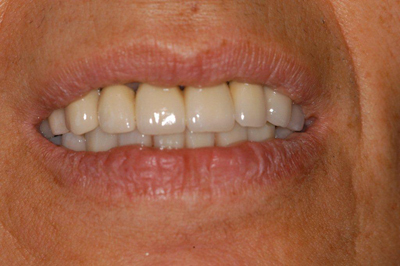

Après

Pose d'implants avant Pose d'implants après